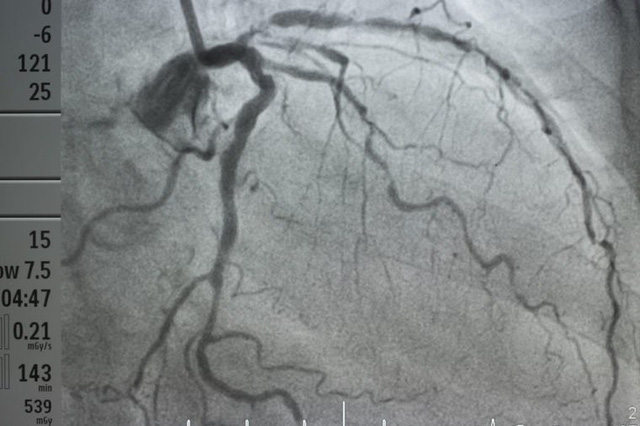

Những dấu hiệu đáng ngạc nhiên của tình trạng tắc động mạch và bệnh tim.